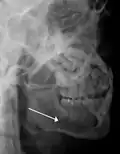

Nondisplaced fracture of the mandible

Traditionally, plain films of the mandible would be exposed but had lower sensitivity and specificity owing to overlap of structures. Views included AP (for parasymphsis), lateral oblique (body, ramus, angle, coronoid process) and Towne's (condyle) views. Condylar fractures can be especially difficult to identify, depending on the direction of condylar displacement or dislocation so multiple views of it are usually examined with two views at perpendicular angles.[11]